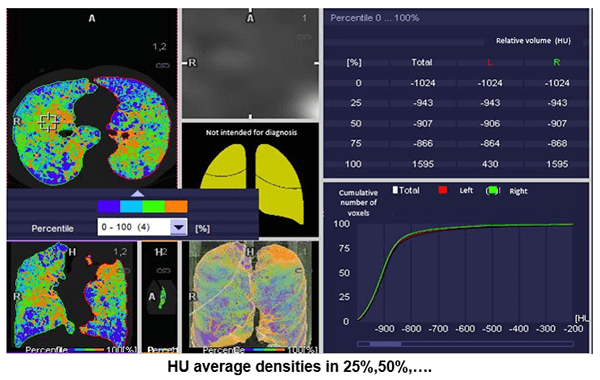

The automated application called “lung density” provides the physician with quantitative data on the volume of pulmonary emphysema, as well as gives us a visual representation of its diffusion.

Damaged Alveoli

This image shows us an example of images where the damaged alveoli are highlighted in blue.

Percentage of Lung Parenchyma

Here, we can see the percentage of lung parenchyma in function of Hounsfield densities.

HU Measurements

This image shows the average density measurements in Hounsfield Units of 25%, 50 %, 75%, and 100%.